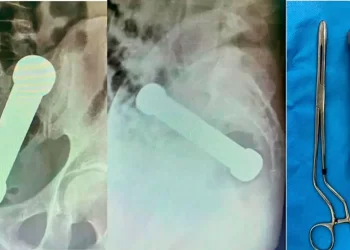

Operaron a un hombre para extraerle una mancuerna tras un peligroso juego sexual

Un ciudadano brasileño tuvo que ser internado de urgencia tras un peligroso juego sexual y debieron operarlo para extraerle una ...